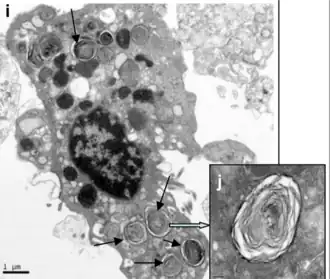

Son de gran importancia por producir el surfactante pulmonar, el cual liberan mediante un mecanismo de exocitosis hacia la luz de los alvéolos.[4]

Se encuentran distribuidos en pequeños grupos entre los neumocitos tipo I. Tienen forma cúbica y poseen microvellosidades en su superficie libre apical. En su interior contienen una serie de vacuolas llamadas citosomas donde almacenan el surfactante pulmonar que secretan al alveolo mediante un proceso de exocitosis. El surfactante pulmonar se mezcla con agua reduciendo su tensión superficial y formando una fina capa que recubre toda la superficie alveolar.